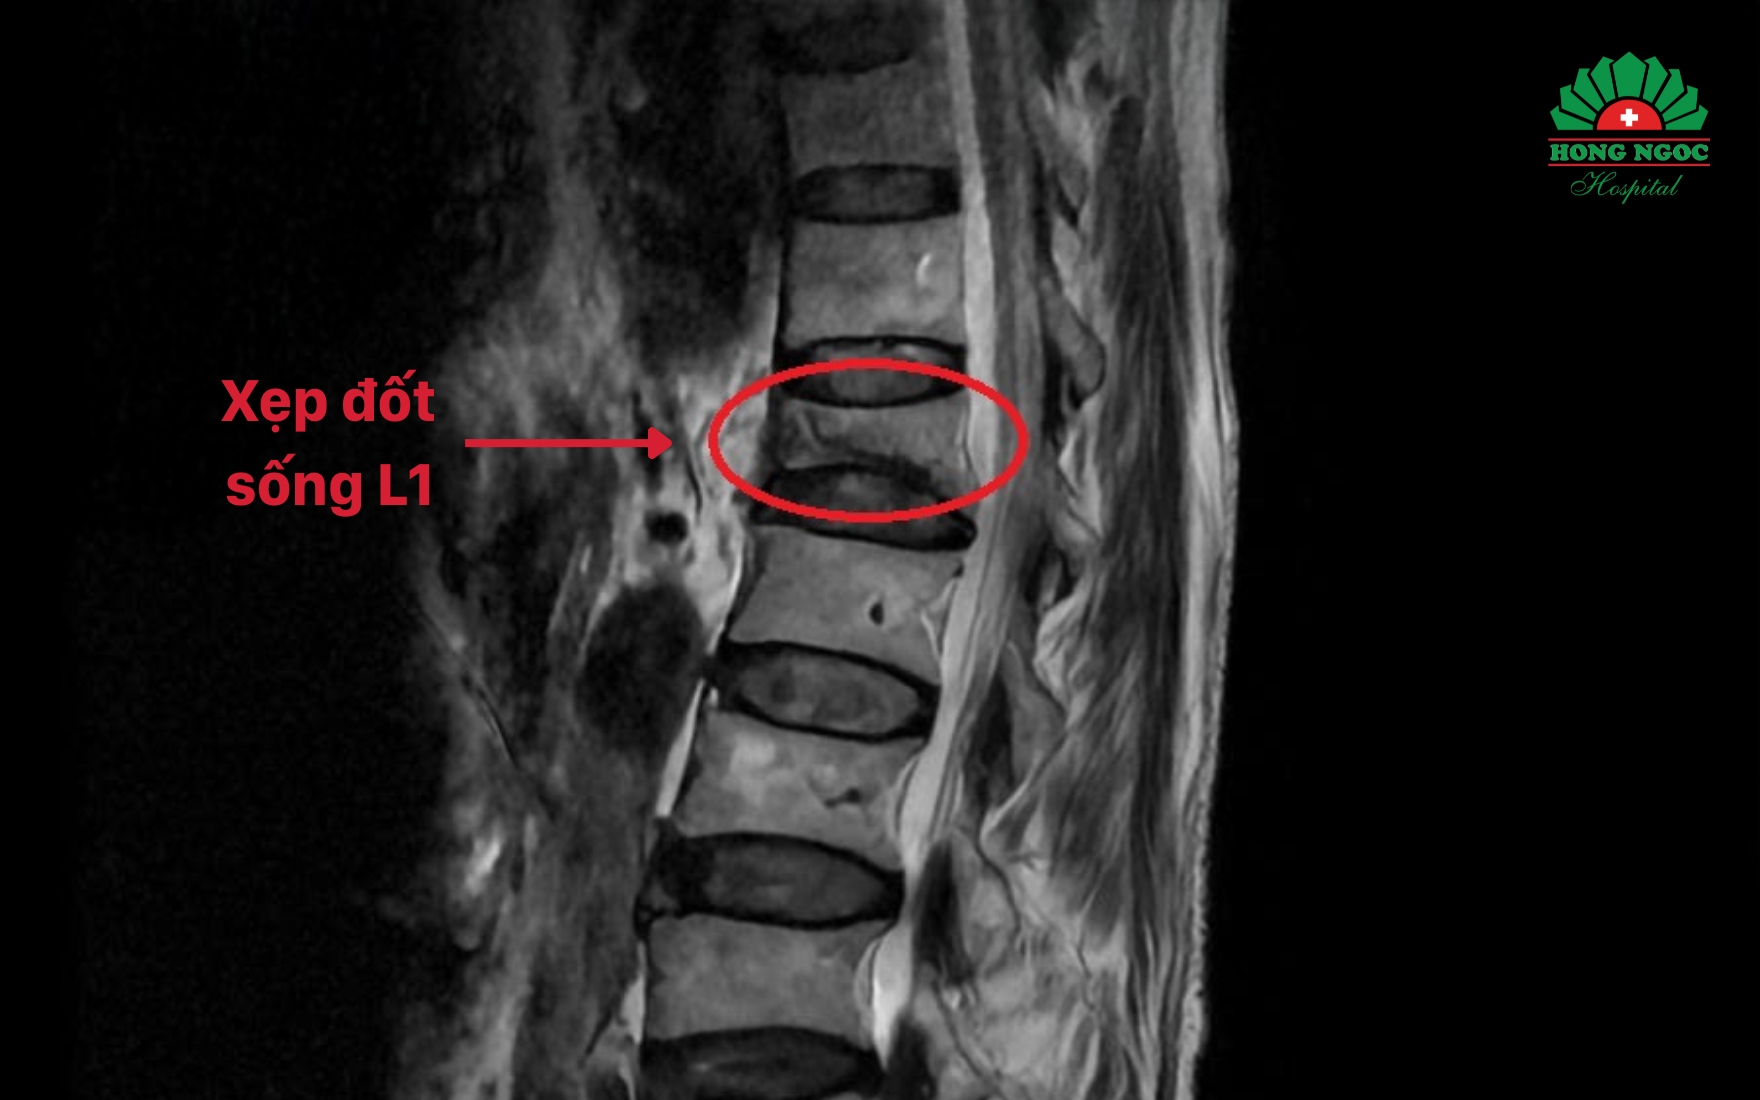

Sau thăm khám lâm sàng, bệnh nhân được chỉ định chụp cộng hưởng từ (MRI) và đo mật độ xương. Kết quả cho thấy ông bị xẹp đốt sống L1, loãng xương mức độ nặng và thoái hóa cột sống thắt lưng.

Kết quả chụp MRI phát hiện xẹp đốt sống L1

Theo TS.BS Trịnh Tú Tâm - Khoa Chẩn đoán hình ảnh & Điện quang can thiệp, BVĐK Hồng Ngọc: "Bệnh nhân bị loãng xương nặng nên cấu trúc xương trở nên yếu, chỉ cần động tác sai tư thế hay một tác động như hắt hơi mạnh cũng có thể khiến xẹp đốt sống. Nếu không điều trị sớm, về lâu dài có thể gây biến dạng chiều cao, gù lưng, thậm chí tàn phế”.